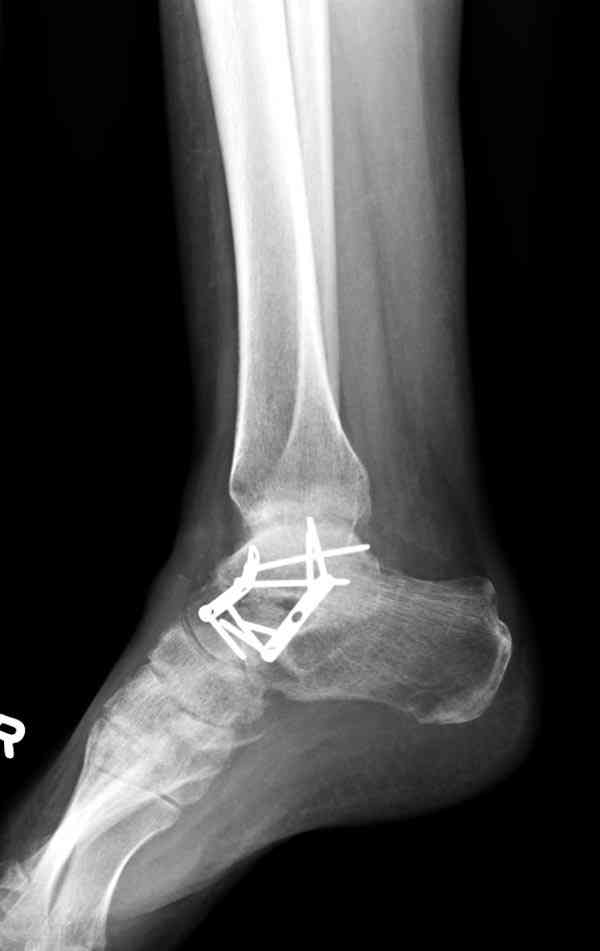

Случай с множественным оскольчатым переломом тарана оперированный из двойного доступа.

Через 8 мес.: